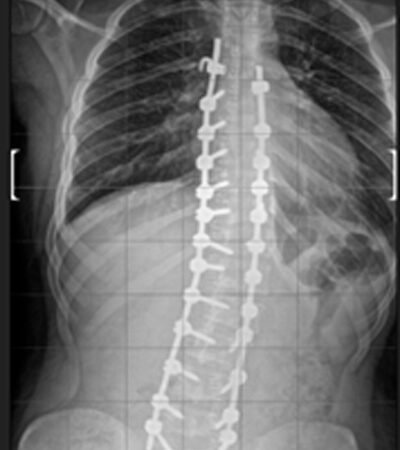

DIAGNOSI:

IPERCIFOSI DORSALE + SCOLIOSI DORSO LOMBARE

Radiografia della colonna in toto pre-operatoria

Intervento chirurgico eseguito:

STABILIZZAZIONE DORSO – LOMBARE CON OSTEOTOMIE CORRETTIVE

Radiografia della colonna in toto post-operatoria